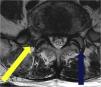

There are several approaches for double disc herniation consisting of an intracanal and foraminal lesion. Of several approaches, we introduced extreme lateral and interlaminar approach (ELIA). And we aimed to compare the approach with the conventional combined interlaminar and paraisthmic approach (CIPA).

Patients and methodsThe authors reviewed the medical charts of patients who underwent a procedure for a double disc herniation at the lumbosacral level between March 2012 and February 2016 and patients who underwent CIPA or ELIA were selected. For preoperative testing, simple X-ray, computed tomography (CT), and magnetic resonance imaging (MRI) scans were performed. For postoperative outcomes, the Korean version of the Oswestry Disability Index (K-ODI) and Numeric Rating Scale (NRS) at one, two, and three months post-operation were checked.